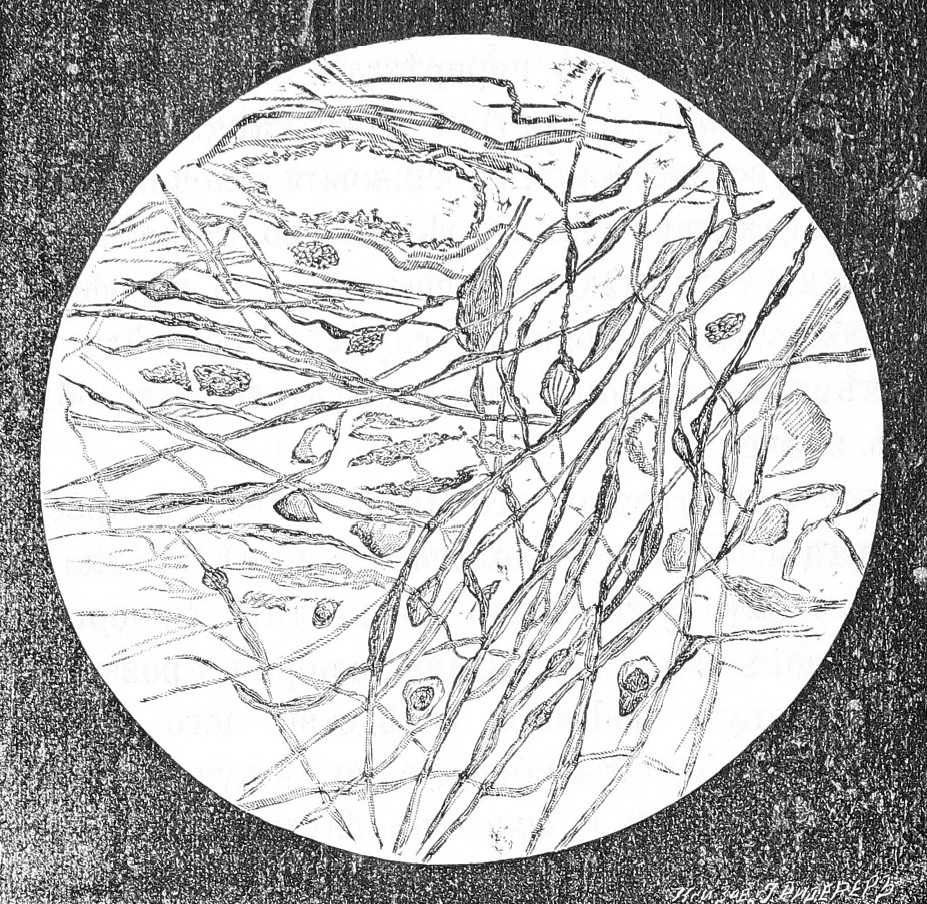

На существованіе перекреста въ швѣ корешковыхъ волоконъ X нерва уже указывалось многими авторами (Schroeder v. d. Kolk 4), Krause[5]), Sehwalbe [6]), Бехтеревъ [7]), Koch [8]), Осиповъ 9). Ramon у Cajal на основаніи изслѣдованій по методу Golgi также признаетъ существованіе перекреста между волоконами X нерва противоположныхъ сторонъ; онъ говоритъ: „конечныя развѣтвленія перекрещиваются большею частью по срединной линіи, образуя настоящій перекрестъ чувствительныхъ корешковъ“. На рисункѣ 13 (стр. 48) въ работѣ Ramon у Cajal’я весьма отчетливо представленъ переходъ корешковыхъ волоконъ блуждающаго нерва черезъ шовъ [10]). Телятникъ въ работѣ „Объ окончаніяхъ языко-глоточнаго нерва въ продолговатомъ мозгу“ на основаніи двусторонней атрофіи тыльныхъ ядеръ IX нерва послѣ вырѣзыванія языко-глоточнаго нерва съ одной стороны приходитъ къ заключенію о существованіи частичнаго перекреста чувствительныхъ корешковыхъ волоконъ языко-глоточнаго нерва [11]). При общности центральныхъ окончаній IX и X пары черепныхъ нервовъ вполнѣ естественнымъ является аналогичное отношеніе ихъ къ ихъ тыльнымъ ядрамъ въ смыслѣ связи тыльнаго ядра каждой стороны съ корешковыми волоками своей стороны и отчасти противоположной. См. рис. 1.

Рис. 1

Тыльная часть поперечнаго срѣза чрезъ продолговатый мозгъ кролика. Окраска по сп. Nissl я.

Справа отъ зрителя—сторона операціи.

- XII—ядра n. hypoglossi

- X—тыльное ядро блуждающаго нерва.

- і. S. —nucl. intercal. Staderini.

На моихъ препаратахъ ядро Staderini также представляетъ атрофическія измѣненія. На срѣзахъ продолговатаго мозга, окрашенныхъ по сп. Nissl’я, въ nucl. intercal. въ изобиліи встрѣчаются сморщенныя, сплошь окрашенныя клѣтки, расположенныя, какъ это видно на рис. I, преимущественно въ тыльной части ядра. Изъ сказаннаго ясно, что nucl. intercal. имѣетъ связь и съ X нервомъ. Если судить по степени атрофіи этого ядра, то наиболѣе тѣсною является его связь съ XII нервомъ, а затѣмъ уже съ IX и X.

Главное ядро XII нерва (ядро Stilling’a) на моихъ препаратахъ представляется на сторонѣ операціи ясно атрофированнымъ въ тыльной своей части, что и представлено на рис. I. Объ этомъ уже было заявлено проф. Бехтеревымъ на основаніи моихъ препаратовъ [16]). Въ настоящее время я убѣдился, что если животное послѣ перерѣзки блуждающаго нерва остается жить довольно продолжителный срокъ (1, 5-2 мѣсяца и далѣе), то атрофія клѣтокъ ядра XII нерва на сторонѣ операціи обнаруживается съ постоянствомъ и очевидностью.